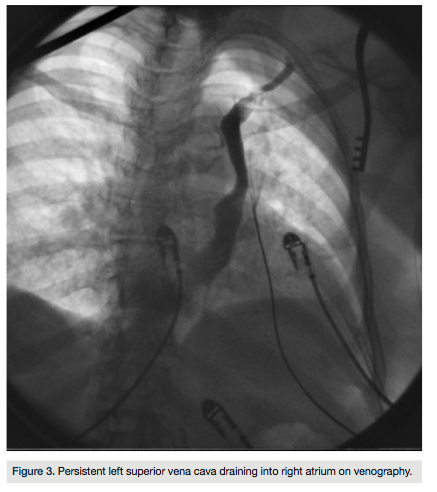

Under fluoroscopic guidance, a left cephalic vein approach was used to gain access to the transvenous route of the heart chambers. While inserting the guide wire, the left subclavian vein had an unusual course, and the guide wire crossed medially behind the heart, suggesting the presence of a persistent left superior vena cava, which was then confirmed by venography (Figure 3). Although a right ventricular pacing lead could still be

placed, an atrial lead could not be positioned superiorly in an optimal position via this approach. The left cephalic vein approach was abandoned and the pacemaker was successfully inserted via the right pectoral approach through the right cephalic vein (Figure 4).